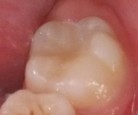

Bệnh nhân: Trần Gia K. 8 tuổi, nam, mã BA 8233/17

Sau ba tháng. ICDAS:2; Di: 21 | Sau sáu tháng. ICDAS:1; Di: 17 | Sau 18 tháng. ICDAS:0; Di: 05 |